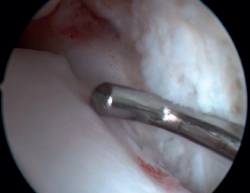

La resección de osteofitos se realiza deslizándose desde su parte superior, rebajando gradualmente hasta alcanzar la zona articular (Figura 2). Con una pinza de tipo basket se puede resecar la zona más cercana a la articulación (Figura 5). Suele ser útil intercambiar los portales de visión y trabajo para visualizar y resecar completamente los osteofitos. Para el pinzamiento de partes blandas, un sinoviotomo de 3,8 o 4 mm suele ser suficiente. El vaporizador es útil en pinzamientos compactos, típicos de condiciones postraumáticas o reintervenciones, también para delimitar la parte ósea del osteofito antes de su resección.

El ligamento de Bassett debe conservarse siempre que no tenga un aspecto patológico, descartando engrosamientos, roturas parciales o lesiones recíprocas en la superficie anterolateral del astrágalo (Figura 6), que se asocian a inestabilidades anterolaterales o rotatorias. La inserción peroneal se usa como referencia para localizar la inserción distal del LTFA. Debe inspeccionarse el ligamento deltoideo en la gotera medial en caso de sospecha de inestabilidad rotatoria asociada. Durante la artroscopia, se puede realizar una reparación directa de los ligamentos mediante suturas y anclajes.

Figura 5. La resección de la parte más cercana al cartílago talar se puede completar con una pinza basket para minimizar el daño del cartílago articular.

Figura 6. Surco producido por el roce de la cúpula talar con el ligamento de Bassett, visible tras la resección de este. El ligamento presentaba una rotura parcial y un engrosamiento cicatricial.